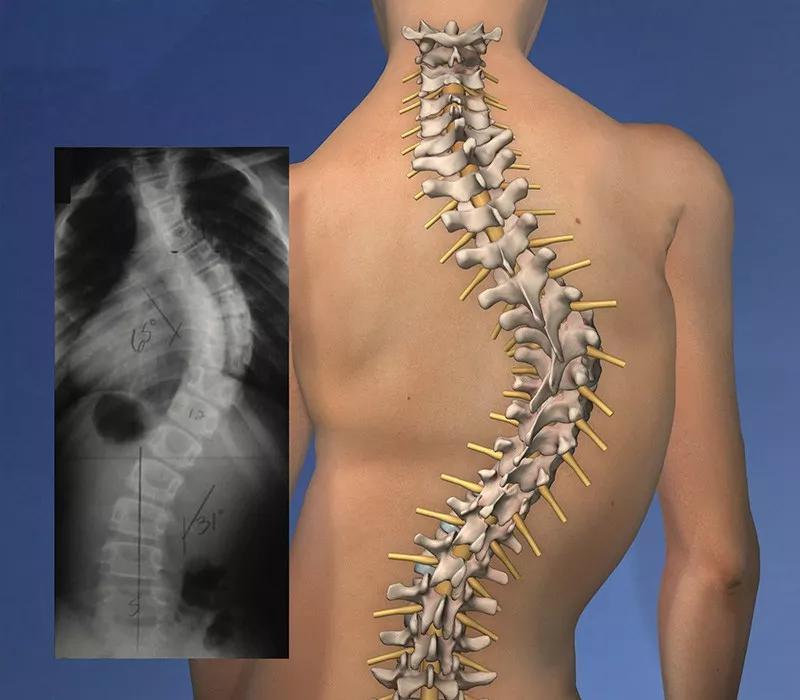

脊椎側彎是一種常見的骨骼問題。

在站姿下,不管從正面或背面看,正常的脊椎排列應該是身體左右兩邊對稱,並且正常的脊椎排列從上到下是呈一直線的。

如果在站姿下看到脊椎向身體的任何一邊彎曲歪斜,就是有可能是脊椎側彎,左右手臂與軀幹之間的空隙不對稱,右側肩膀較高。

然而大部分的脊椎側彎並不只有單一平面的左右傾斜,通常會伴隨着脊椎旋轉,往往也會影響到肩胛骨的動作,導致肩關節的活動度受限。